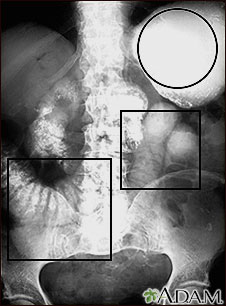

This abdominal X-ray shows a stomach filled with fluid and a swollen (distended) small bowel, caused by a blockage (pseudo-obstruction) in the intestines. A solution containing a dye (barium) that is visible on X-rays was swallowed by the patient (upper GI series).